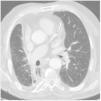

The patient has been followed-up regularly for the last 11 years, and has suffered recurrent respiratory infections recovering easily with antibiotherapy. Serial chest CT scans (Fig. 3), showed an unaltered diffuse density in the subcarinal and right hilar regions extending to the right pulmonary artery, thought to be scarring. The patient has refused to undergo further bronchial endoscopy.